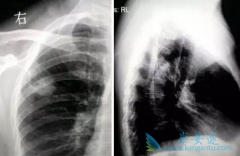

为了评估EGFR突变阳性NSCLC患者一线 厄洛替尼 (GRLONAT)疗法可靠有效性,以及疾病发生进展后厄洛替尼疗法的治疗效果,Keunchil Park教授等开展了一项开放性单组II期临床研究——ASPIRATION研究项目。研究人员纳入2011年-2012年间,涵盖香港、韩国、台 ...